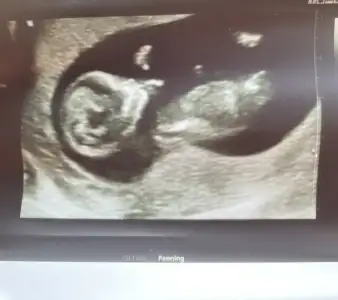

Ay bizimki ne sence o zamanPozisyon şubaşı öne eğik olunca sanırım kız olur demek istedi. Bizimkinin ayakları havada

Yok mu tahmin edebilenMerhaba sevgili mart anneleri bebeğimin 10+2 de ultrason fotoğrafı cinsiyet tahmini yapabilen var mı acaba çok merak ediyorum![]()